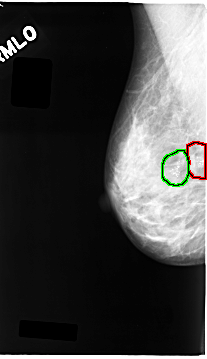

FILE: C_0063_1.RIGHT_MLO.OVERLAY

TOTAL_ABNORMALITIES 2

ABNORMALITY 1

LESION_TYPE CALCIFICATION TYPE PLEOMORPHIC DISTRIBUTION CLUSTERED

ASSESSMENT 5

SUBTLETY 5

PATHOLOGY MALIGNANT

TOTAL_OUTLINES 1

BOUNDARY

ABNORMALITY 2